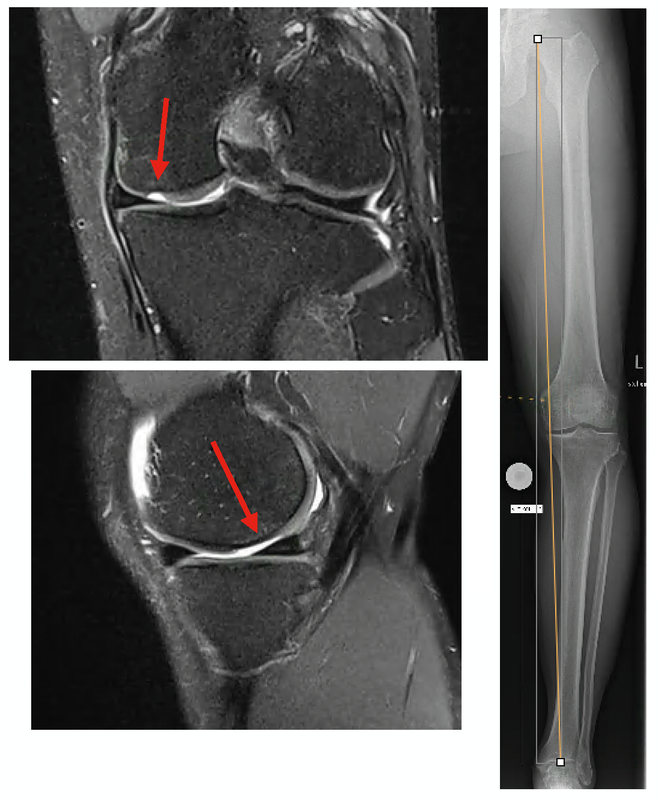

The clinical articles span arthroscopic and reconstructive techniques across major joints. Current techniques in arthroscopic Bankart repair address shoulder instability management, while modern cartilage repair combined with realignment osteotomy of the knee joint and biplanar opening-wedge tibial valgus osteotomy for medial knee OA examine lower limb preservation strategies. The issue concludes with a critical appraisal of femoro-acetabular impingement (FAI), evaluating the continued role of open surgery in contemporary practice.